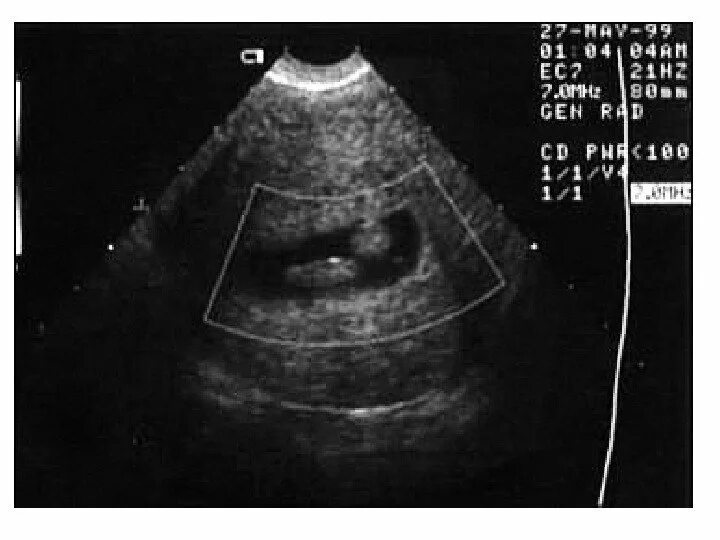

Как выглядит полип на узи